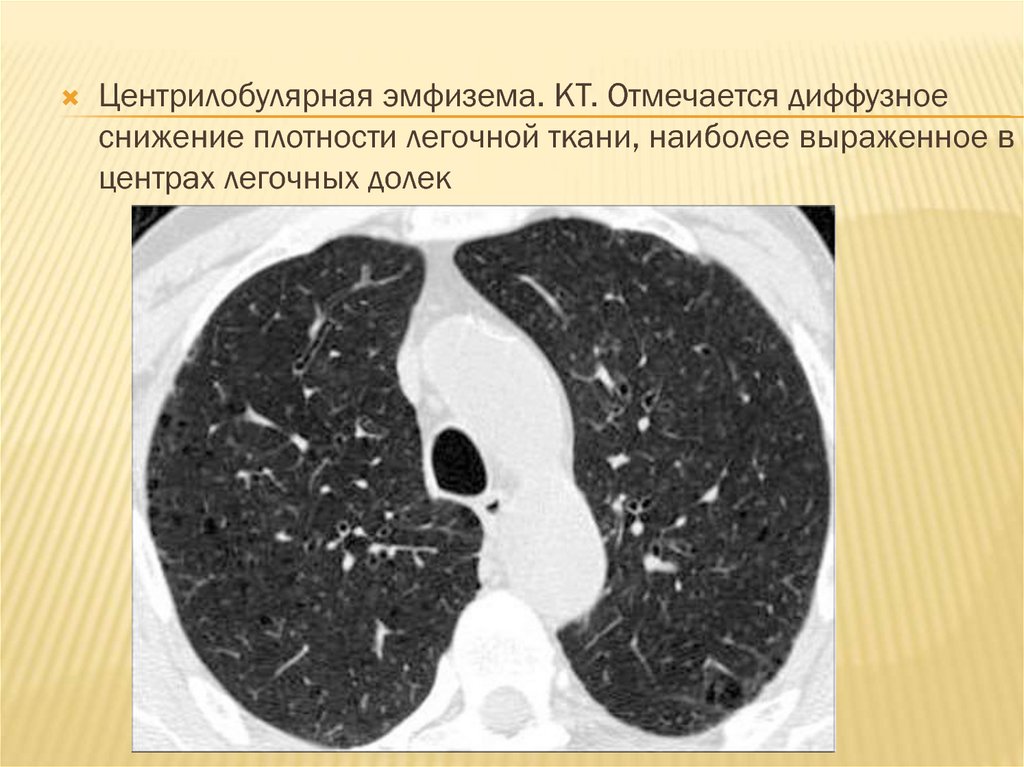

Эмфизема легких

Эмфизема легких.

ХОБЛ - эмфизема легких на КТ заключении грудной клетки (КТ второе мнение)